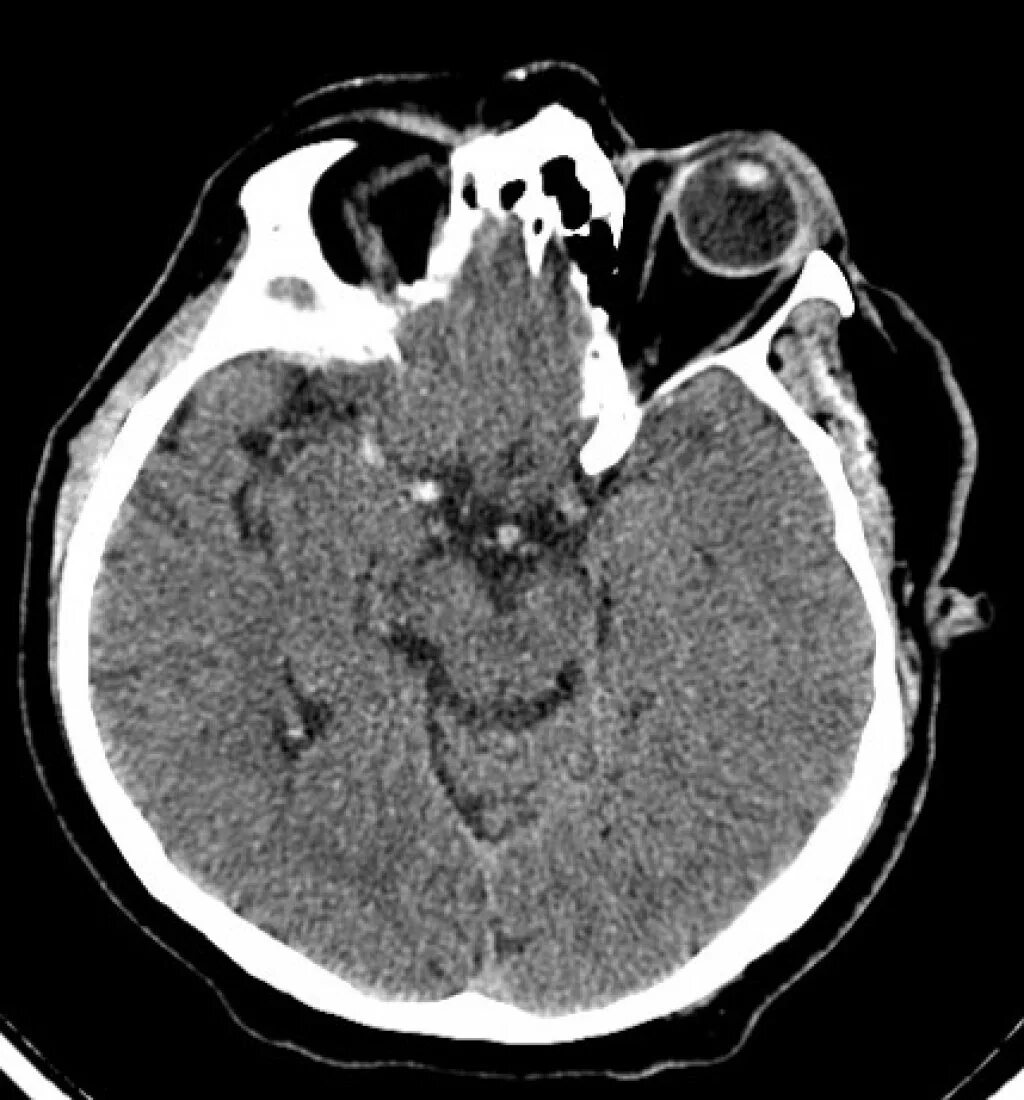

Онмк в бассейне сма